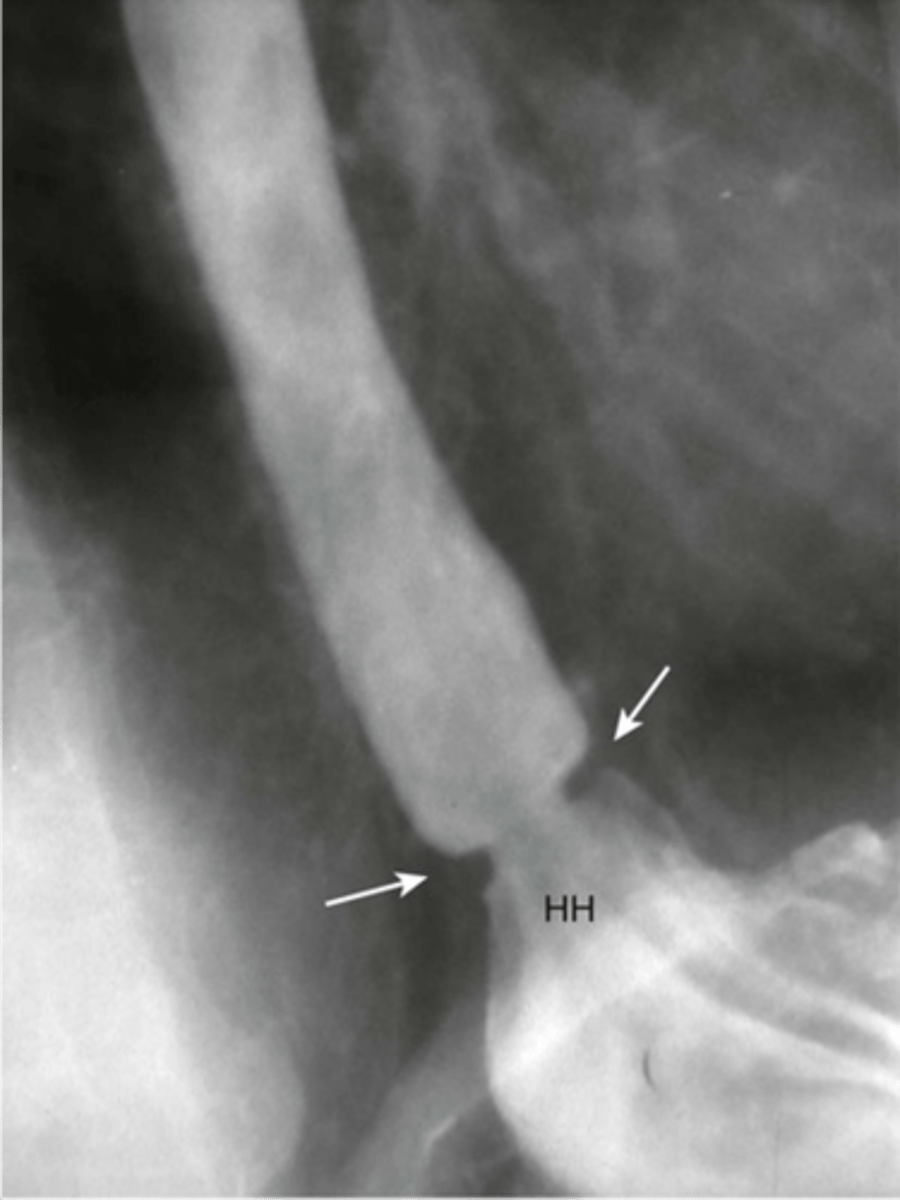

Hiatal hernia

Sliding hiatal hernia

Sliding hiatal hernia (pic 2)

Sliding hiatal hernia (pic 3)